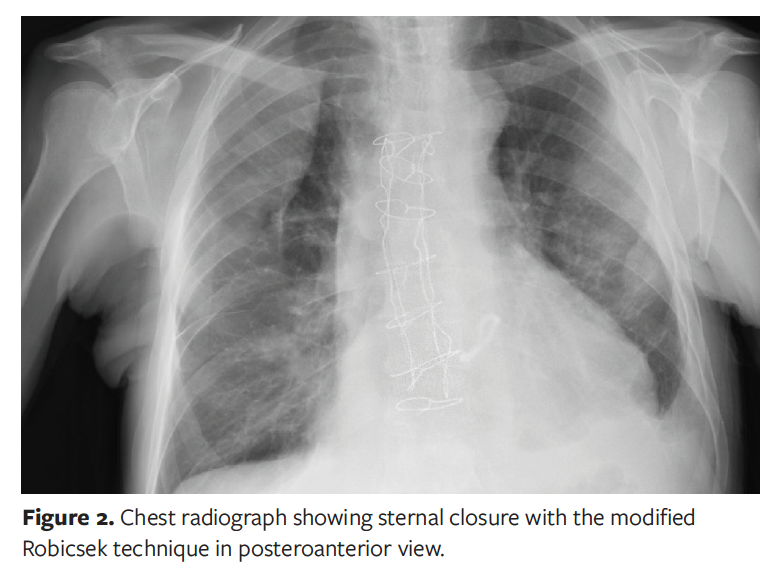

For the modified Robicsek technique, 2 wires were placed parasternally on each side of the sternal bone and passed in an alternating manner anteriorly and posteriorly to the costal cartilages, from the upper sternal edge down to the xiphoid process (Figure 2).15 Each wire was then reversed and directed back towards the jugular notch and the cranial sternal edge, passing the wire anteriorly if it had been previously placed posteriorly and vice versa. The 2 ends of each wire were then tied together at the superior border of the first rib, after which a variable number of parasternal wires were passed and tied in the usual manner.15